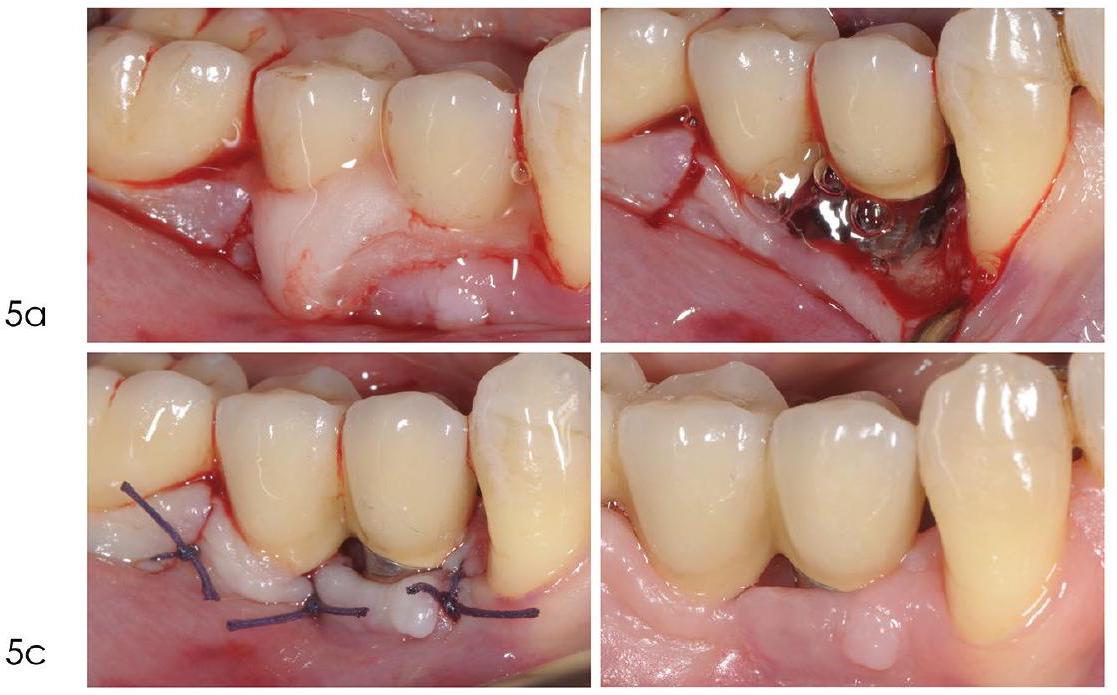

Access flap debridement without resective procedures

is decontaminated using mechanical, chemical, and potentially other adjunctive methods such as photodynamic therapy or laser treatment. The flap is then repositioned and sutured in place.

Access flap debridement with resective procedures

Comparative studies have evaluated the efficacy of implantoplasty against alternative decontamination with air-polishing with glycine powder.

- In case of insufficient keratinised mucosa width, a connective tissue graft should be trimmed and adapted over the entire defect so as to cover

of the surrounding alveolar bone to ensure stability of the graft material. Should the defect be circumferential in an area with no keratinised mucosa, a large connective tissue graft could be punched, by means of a circular blade, and adapted circumferentially around the defect - Patients should be instructed on how to protect, care for, and keep clean the surgical

site so as to favour primary healing of the surgical wound.

step of care, as it creates better peri-implant conditions before surgical intervention.

to facilitate the long-term maintenance and to preserve aesthetics.